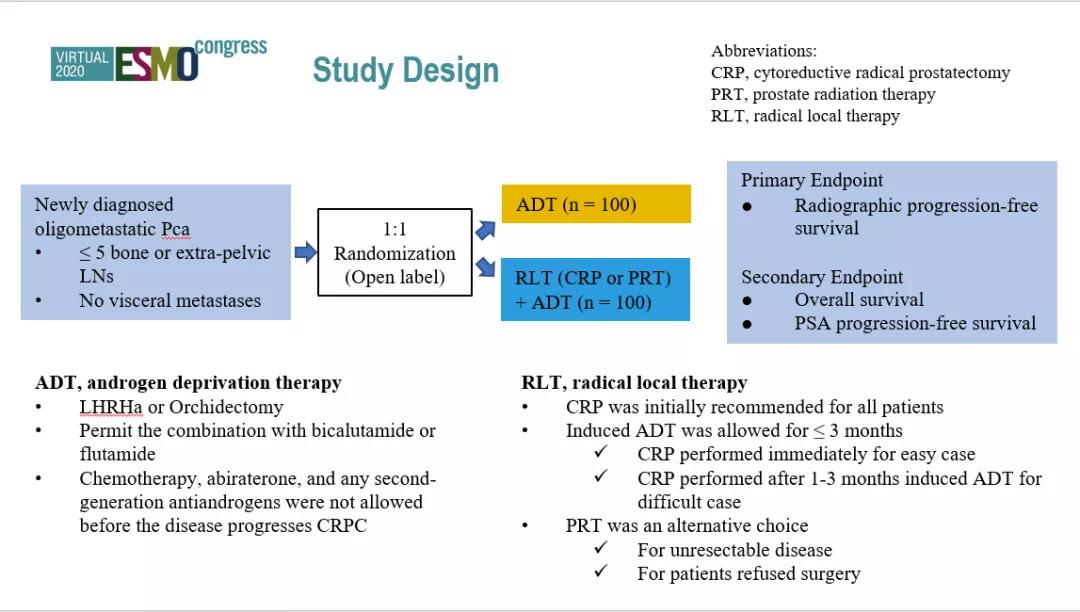

由复旦大学附属肿瘤医院泌尿外科叶定伟教授、戴波教授团队开展的“初诊寡转移性前列腺癌接受原发灶局部治疗的随机对照开放标签2期临床研究”在今年的ESMO大会上获得了口...